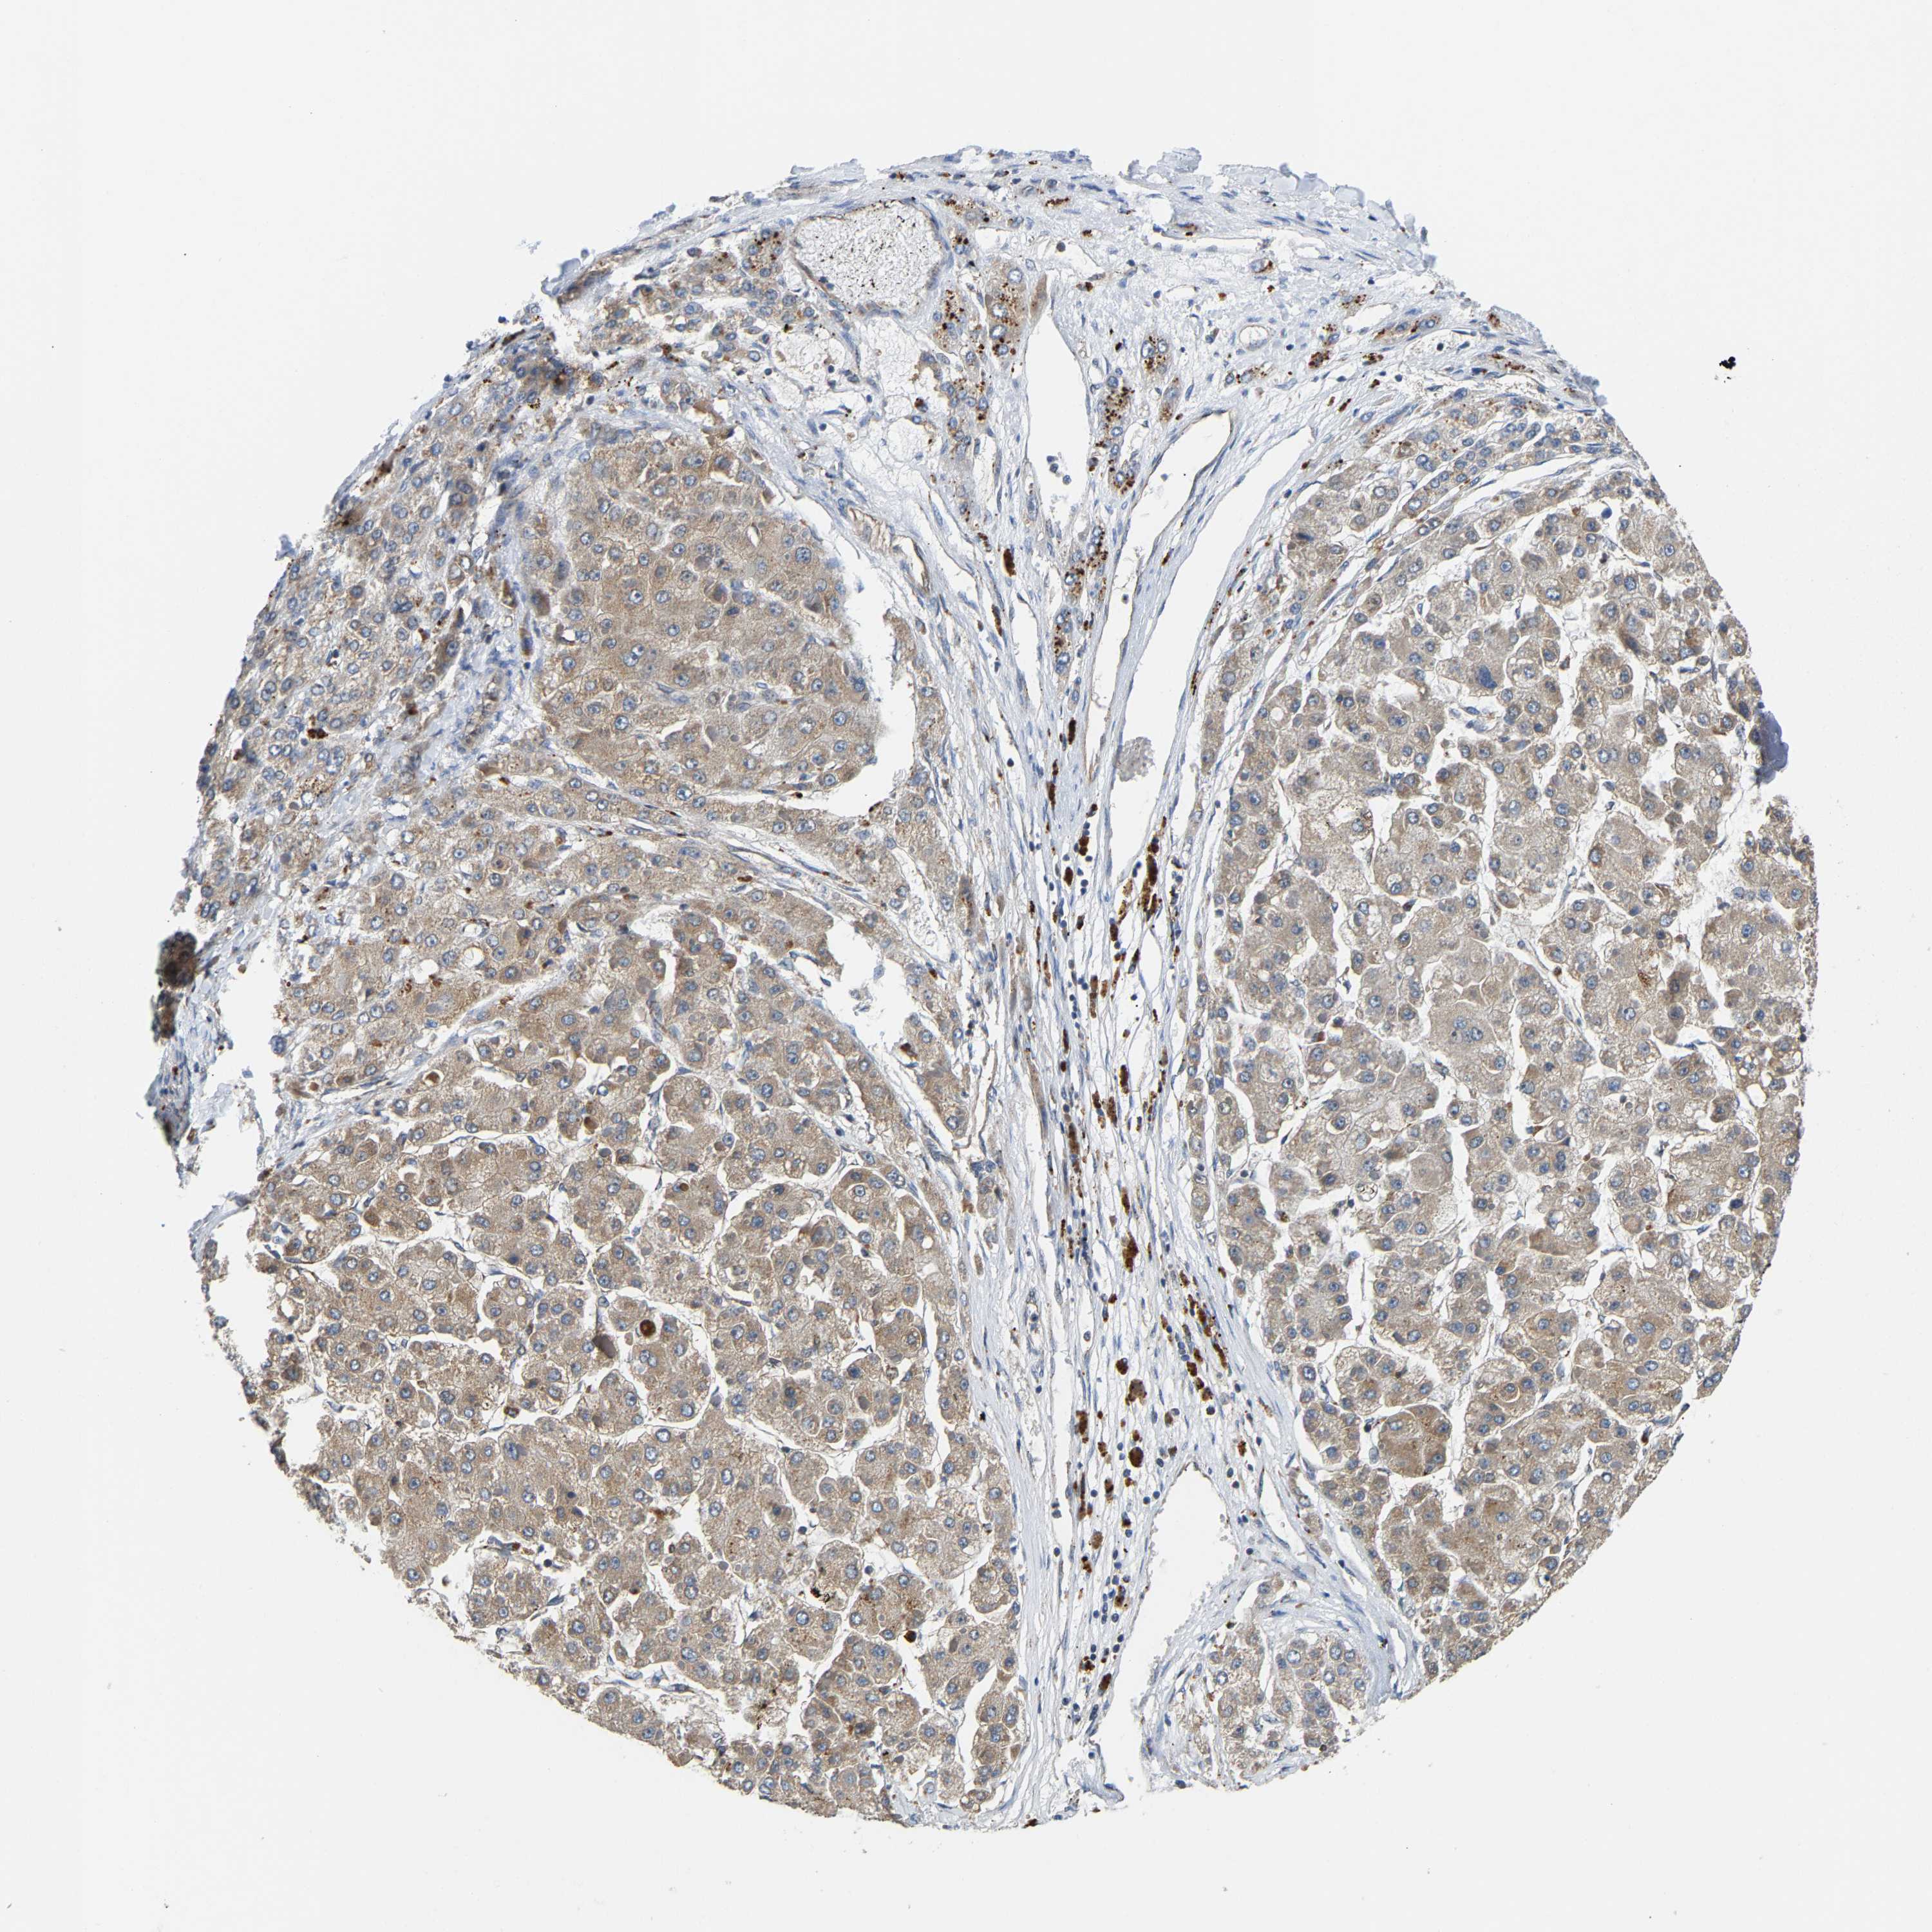

LIVER CANCER - Protein expressioni

A mouse-over function shows sample information and annotation data. Click on an image to view it in a full screen mode. Samples can be filtered based on level of antibody staining by selecting one or several of the following categories: high, medium, low and not detected. The assay and annotation is described here.

Antibody stainingi

Antibody staining in the annotated cell types in the current human tissue is reported as not detected, low, medium, or high, based on conventional immunohistochemistry profiling in selected tissues. This score is based on the combination of the staining intensity and fraction of stained cells.

Each image is clickable and will lead to virtual microscopy that enables deeper exploration of all samples and also displays staining intensity scores, fraction scores and subcellular localization as well as patient and tissue information for each sample.

Antibody HPA020266

Antibody HPA020268

Staining

High

Medium

Low

Not detected

Intensity

Strong

Moderate

Weak

Negative

Quantity

>75%

75%-25%

<25%

None

Location

Nuclear

Cytoplasmic/membranous

Cytoplasmic/membranous,nuclear

Cholangiocarcinoma

Carcinoma, Hepatocellular, NOS